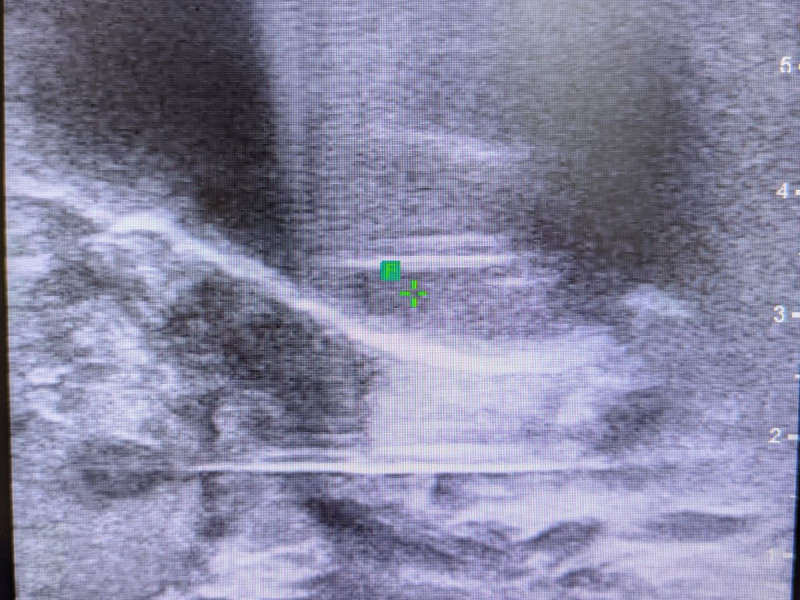

Die perineale Fusionsbiopsie ist eine sichere und präzise Methode zur Entnahme von Prostatagewebe bei Verdacht auf Prostatakrebs. Mit der Kombination von MRT- und Ultraschallbildern können zielgenau Prostatagewebe-Proben entnommen werden (siehe Bild). Unter Echtzeit-Darstellung der Prostata mit einer hochauflösenden Ultraschallsonde wird die perineale (durch den Damm) Fusionsbiopsie durchgeführt. Dies erfolgt über lediglich zwei Einstiche im betäubten Dammbereich, nicht durch den Enddarm. Das macht den Eingriff angenehmer und ermöglicht eine Biopsie ohne Antibiotika-Gabe.

Bild: Darstellung der Probenentnahme aus einem auffälligen Prostata Bereich über den Damm.